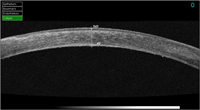

Figura 2), opacidades corneales estromales y su profundidad, patologías asociadas al LASIK (

Figura 3 y

Figura 4, fase infecciosa de una queratitis estromal en la interfase y posterior resolución) y desprendimientos de la membrana Descemet, entre otras muchas patologías.

Figura 3. Infección en operado de LASIK.